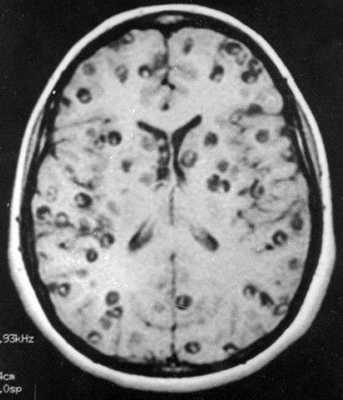

о Диссеминированная форма (также известна как милиарный НЦЦ): редко